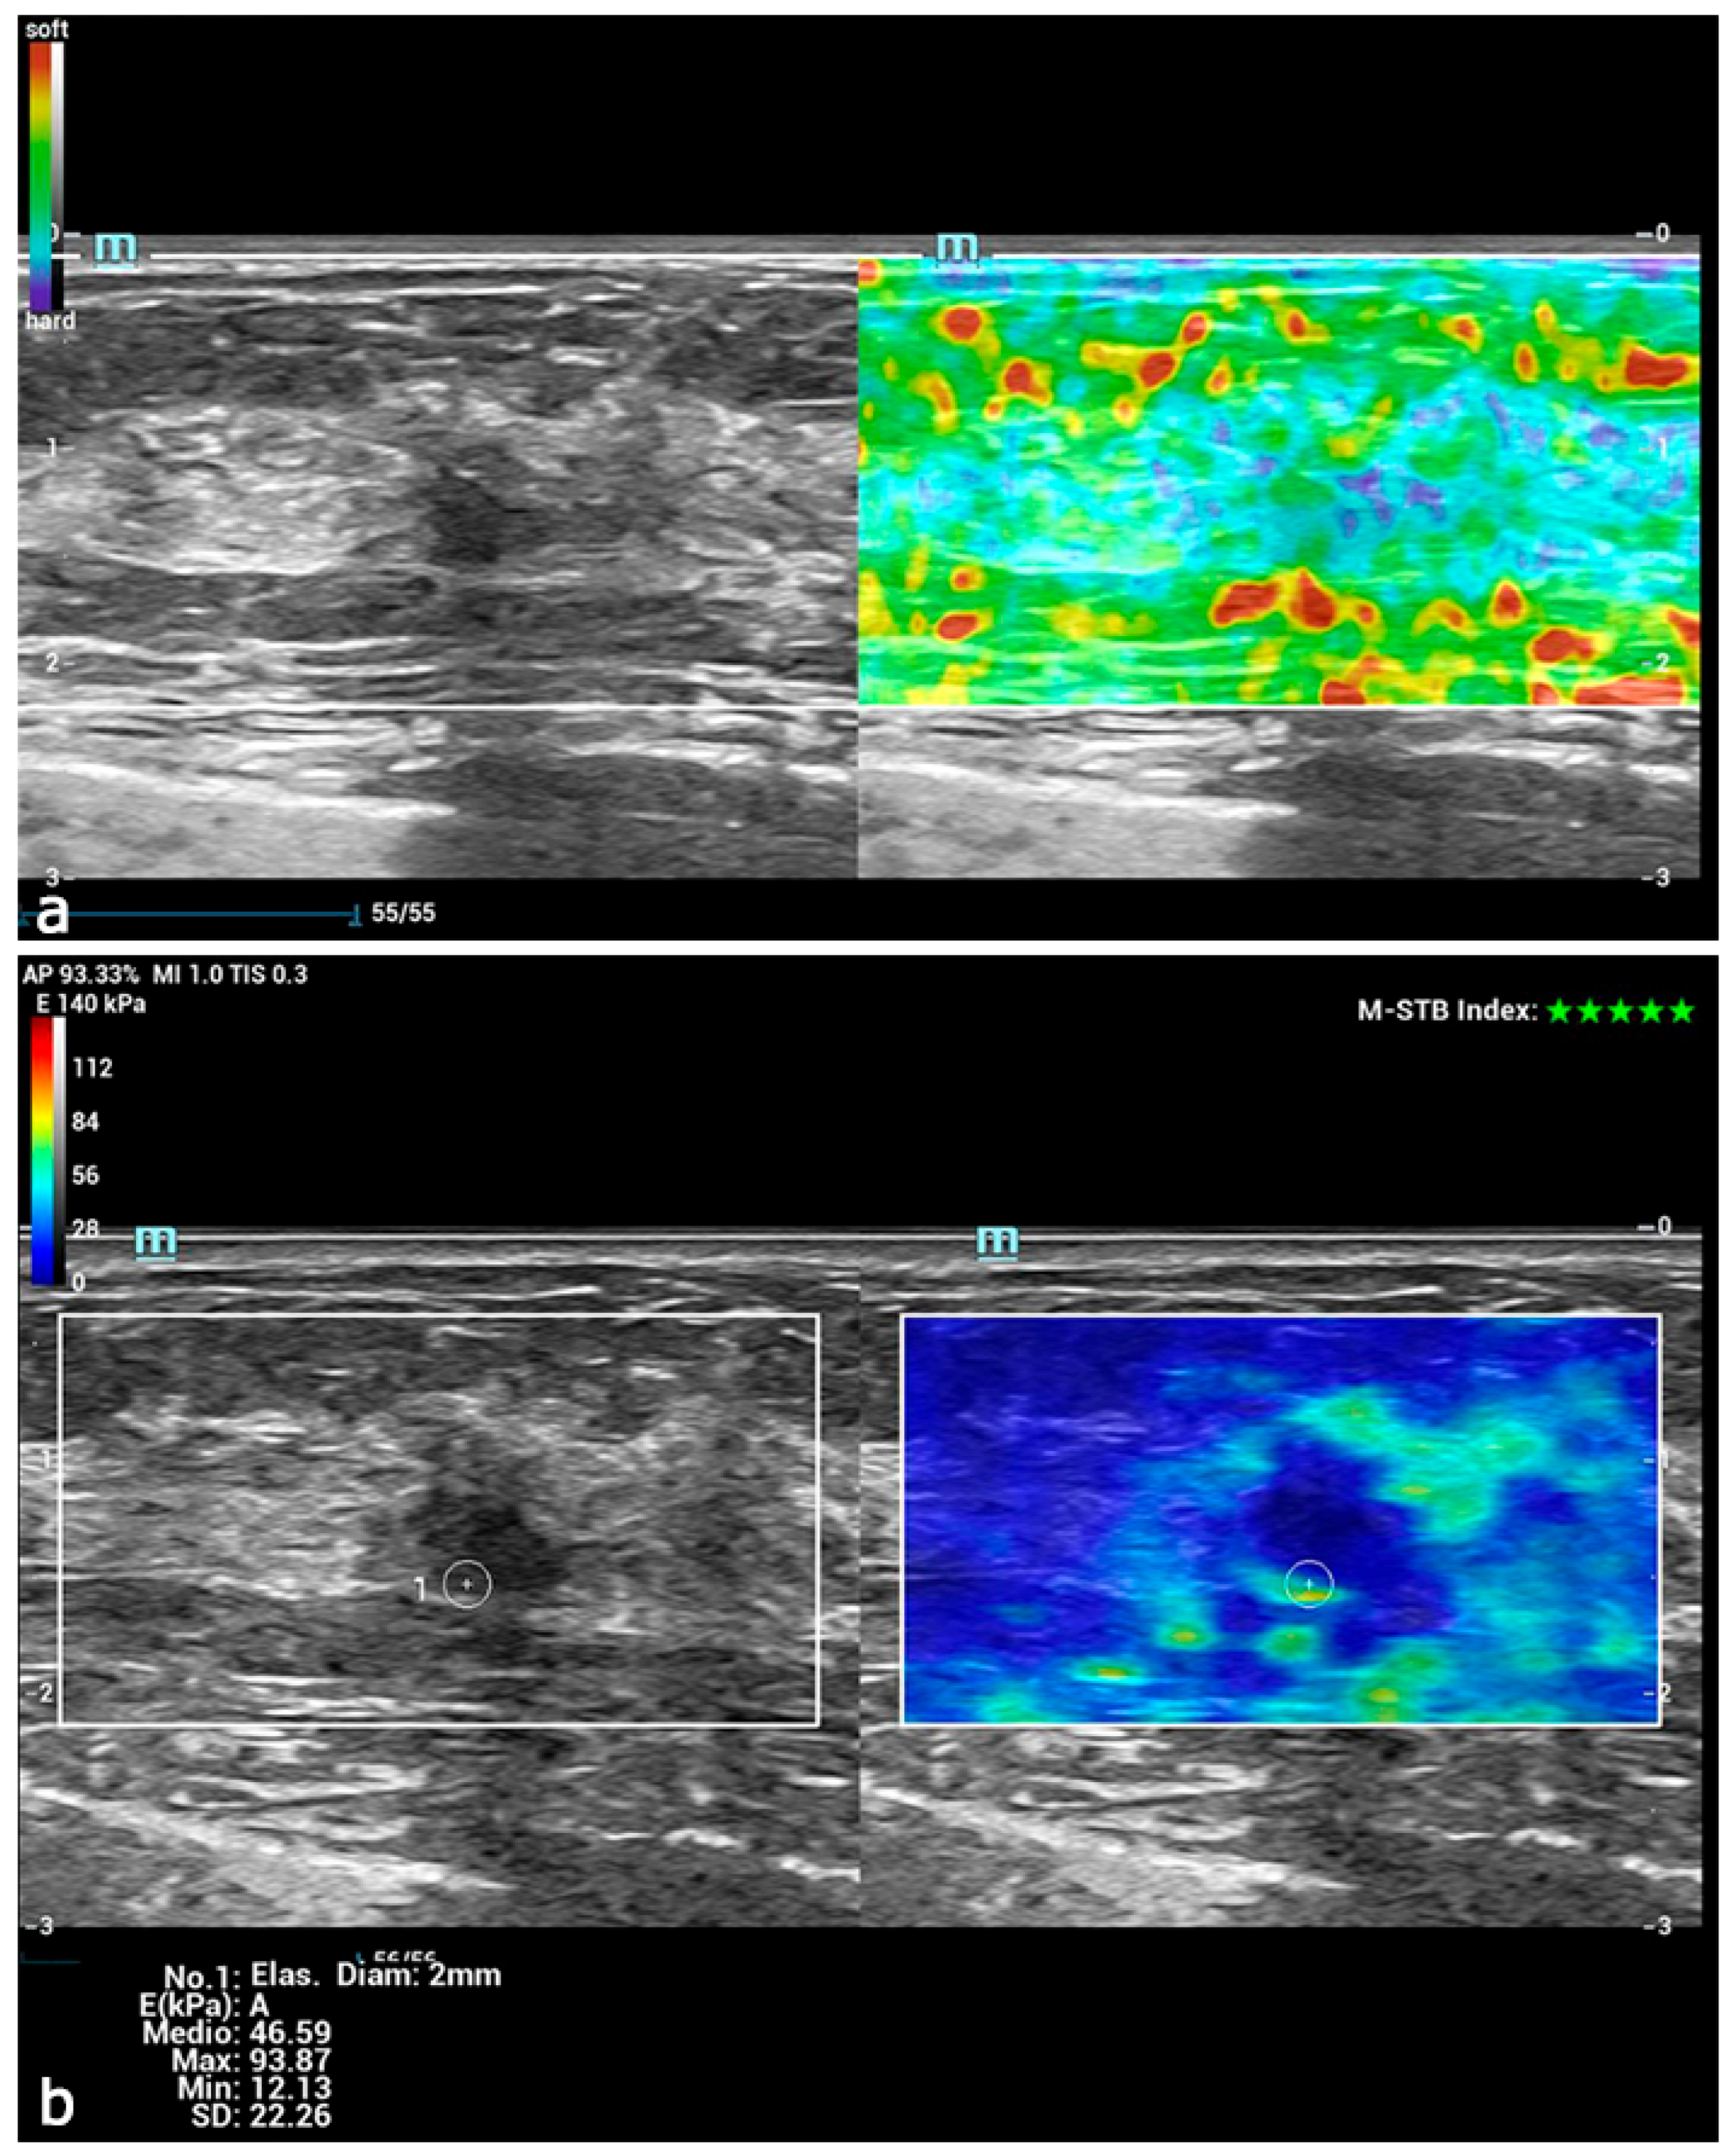

- Youk, J.H.; Gweon, H.M.; Son, E.J.; Han, K.H.; Kim, J.-A. Diagnostic value of commercially available shear-wave elastography for breast cancers: Integration into BI-RADS classification with subcategories of category 4. Eur. Radiol. 2013, 23, 2695–2704. [Google Scholar] [CrossRef]